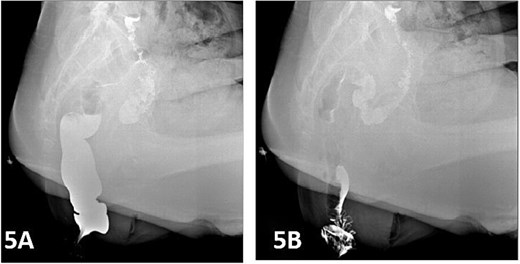

Postoperatively, the patient was administered intravenous cefuroxime and metronidazole for 3 days as prophylactic antimicrobial therapy. The iodine-impregnated vaginal gauze pack and indwelling urinary catheter were removed 24 h after surgery. Daily vaginal dressing changes were performed, involving thorough wound disinfection with povidone-iodine. In cases of excessive vaginal discharge, additional irrigation with normal saline was conducted. The interrupted silk sutures on the posterior vaginal wall were removed during a follow-up visit 2 weeks postoperatively. At 15 days postoperatively, following suture removal, repeat defecography demonstrated a residual RC depth of 11 mm, with complete resolution of the patient’s defecatory dysfunction (Fig. 5). During the 24-month postoperative follow-up period, the patient maintained normal defecatory function with no recurrence of obstructive symptoms. However, repeat defecography was not performed due to the patient’s personal preference.

Postoperative defecography at 15 days, the image demonstrates a residual RC depth of 11 mm.